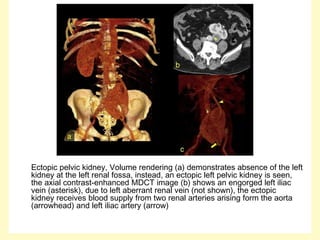

Ectopic pelvic kidney, Volume rendering (a) demonstrates absence of the left

kidney at the left renal fossa, instead, an ectopic left pelvic kidney is seen,

the axial contrast-enhanced MDCT image (b) shows an engorged left iliac

vein (asterisk), due to left aberrant renal vein (not shown), the ectopic

kidney receives blood supply from two renal arteries arising form the aorta

(arrowhead) and left iliac artery (arrow)